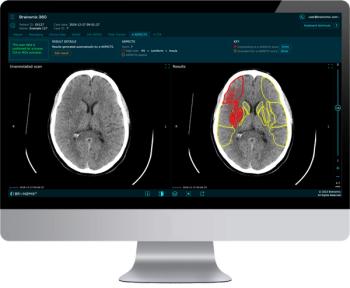

In a recent video interview, Kathy Schilling, M.D., discussed findings from a study of ProFound AI, an adjunctive artificial intelligence (AI) software for digital breast tomosynthesis (DBT), that demonstrated a 23 percent increase in breast cancer detection in comparison to DBT alone.